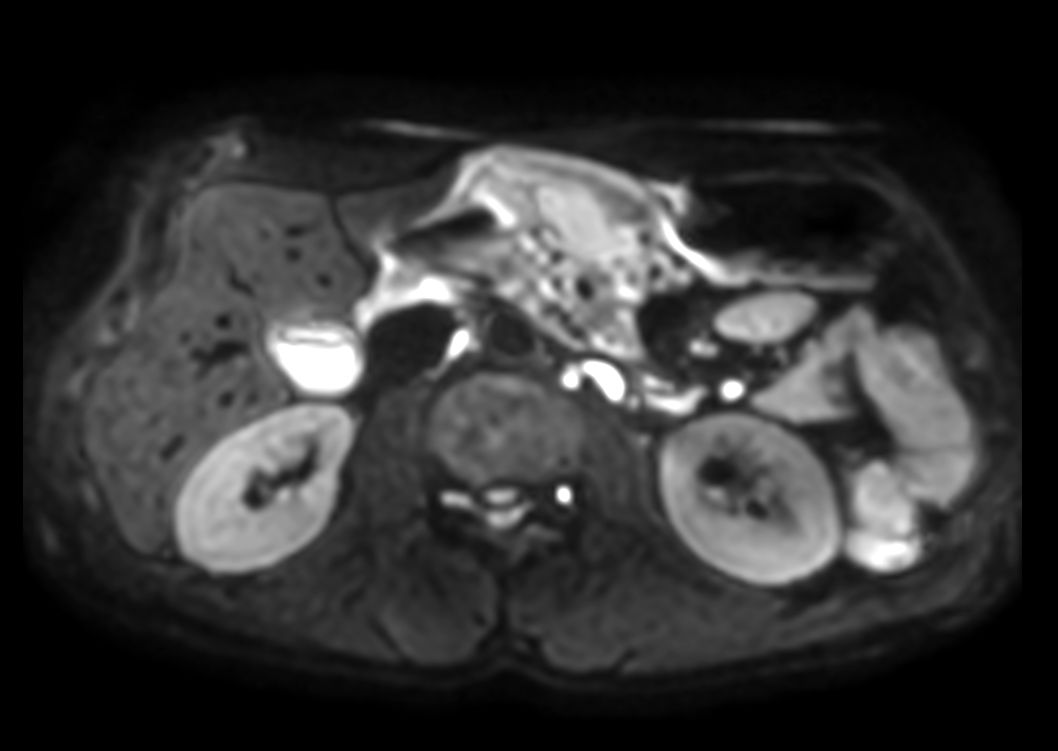

Axial DWI b10003mm slices

-

Axial DWI b503mm slices

Axial DWI b6003mm slices

Axial DWI ADC3mm slices

Axial DWI b504mm slices

Axial DWI b6004mm slices

Axial DWI ADC4mm slices